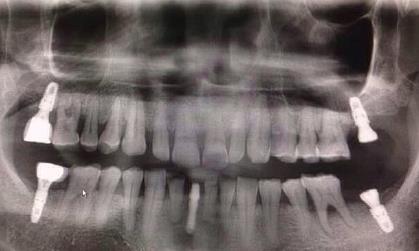

深圳牙科醫院醫生解答,一般種植牙是沒有年齡限製,無論是中成年人,還是老年人都是可以做種植牙的,但是未成年人是不可以的,這是適應症要求。種植牙的使用證要求,還有如果是高齡老人,需要排查全身疾病,比如說糖尿病、高血壓、腦血管病、心髒病等,需要控製在一定範圍內(nei) ,才能酌情考慮。

但是比起中年人,老年人要麽(me) 是因為(wei) 長期不修複牙齒缺失,要麽(me) 是長期佩戴活動假牙,導致牙齦萎縮、牙槽骨吸收嚴(yan) 重,所以有的老年人牙槽骨骨量不夠,想要做種植牙,是需要做植骨手術的;如果是有嚴(yan) 重牙周炎的,也需要及時治療,控製在一定範圍。

此外,老年人和年輕人在恢複能力以及新陳代謝能力等各方麵都存在很大的差異了,老年人恢複可能比較慢,而且如果有骨質疏鬆的情況,牙槽骨萎縮比較嚴(yan) 重。但是並不是說不可以做,一般需要全麵檢查後才能有效確定。其實大部分的老年人**情況如果滿足條件,能夠耐受手術,選擇專(zhuan) 業(ye) 的種植牙醫生,就是可以放心的。